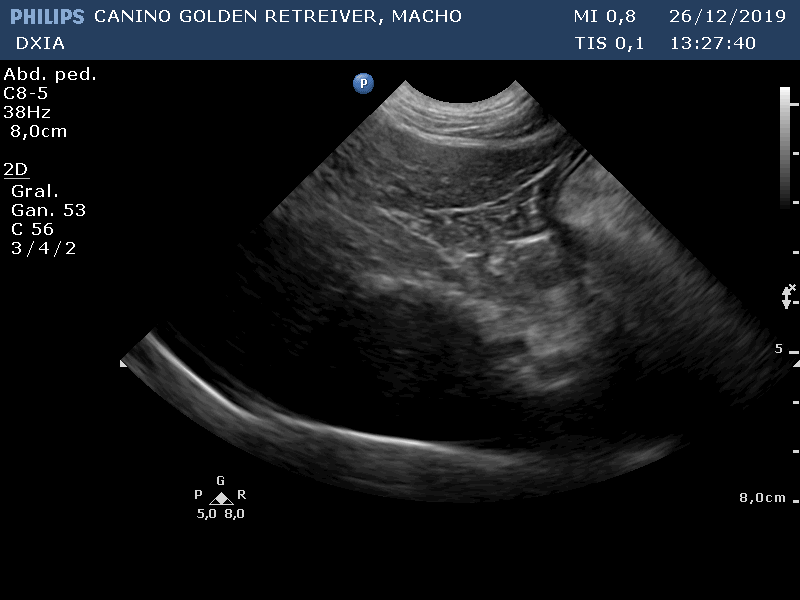

Durante los estudio ecográficos se observa marcada mejoría del parénquima hepática con reducción de la zona afectada y disminución de ese aspecto nodular observado en estudios previos.

Estas son varias imágenes obtenidas del parénquima hepático:

Revisión Imagen Hígado DXIA Scoot

Revisión Imagen Hígado a mitad de quimio